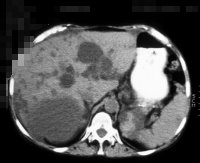

Die Diagnose wird mittels Anamnese (zystische Nierenerkrankungen in der Familie), RR-Messung, Labor (Kreatinin) mit genetischer Untersuchung, Sonographie, Computertomographie und gegebenfalls Kernspintomographie gestellt (Abbildung 4).